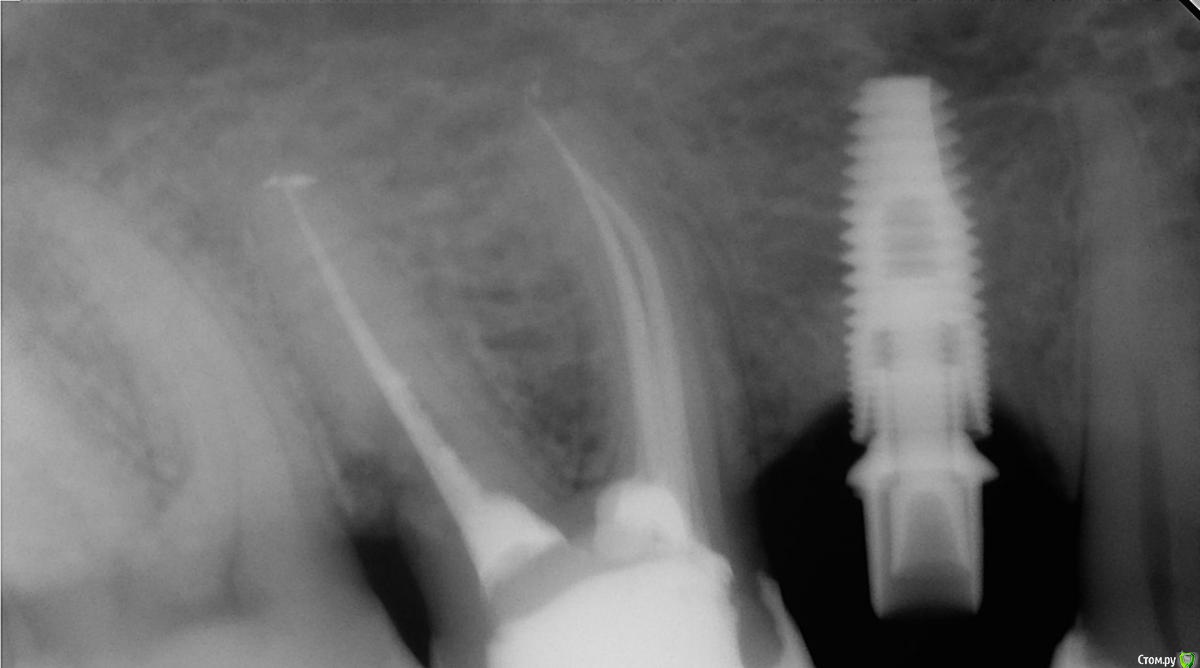

Romanson Опубликовано 30 сентября, 2016 Поделиться Опубликовано 30 сентября, 2016 Дабы не плодить темы, спрошу в этой.Подскажите пожалуйста, что за система? Подходит отвертка от MIS Ссылка на комментарий

Bier Опубликовано 3 октября, 2016 Поделиться Опубликовано 3 октября, 2016 а разве там родные абатмент и трансфер? такое чувство, что у имплантата конус, а у супраструктур обычный 6гранник 6 Ссылка на комментарий

Troy Опубликовано 3 октября, 2016 Поделиться Опубликовано 3 октября, 2016 а разве там родные абатмент и трансфер? такое чувство, что у имплантата конус, а у супраструктур обычный 6гранникПрикол но так и есть Ссылка на комментарий

Romanson Опубликовано 5 октября, 2016 Поделиться Опубликовано 5 октября, 2016 Судя по всему так и есть Ничего не знаю про этот случай. Коллеги попросили спросить на форуме, вдруг кто подскажет. Ссылка на комментарий

ReaperGanzA Опубликовано 6 октября, 2016 Поделиться Опубликовано 6 октября, 2016 Дабы не плодить темы, спрошу в этой.Подскажите пожалуйста, что за система? Подходит отвертка от MISТрансфер от мисовского шестигранника, а вот болт похож на мисовский С1, в последнем есть сомнения 1 Ссылка на комментарий